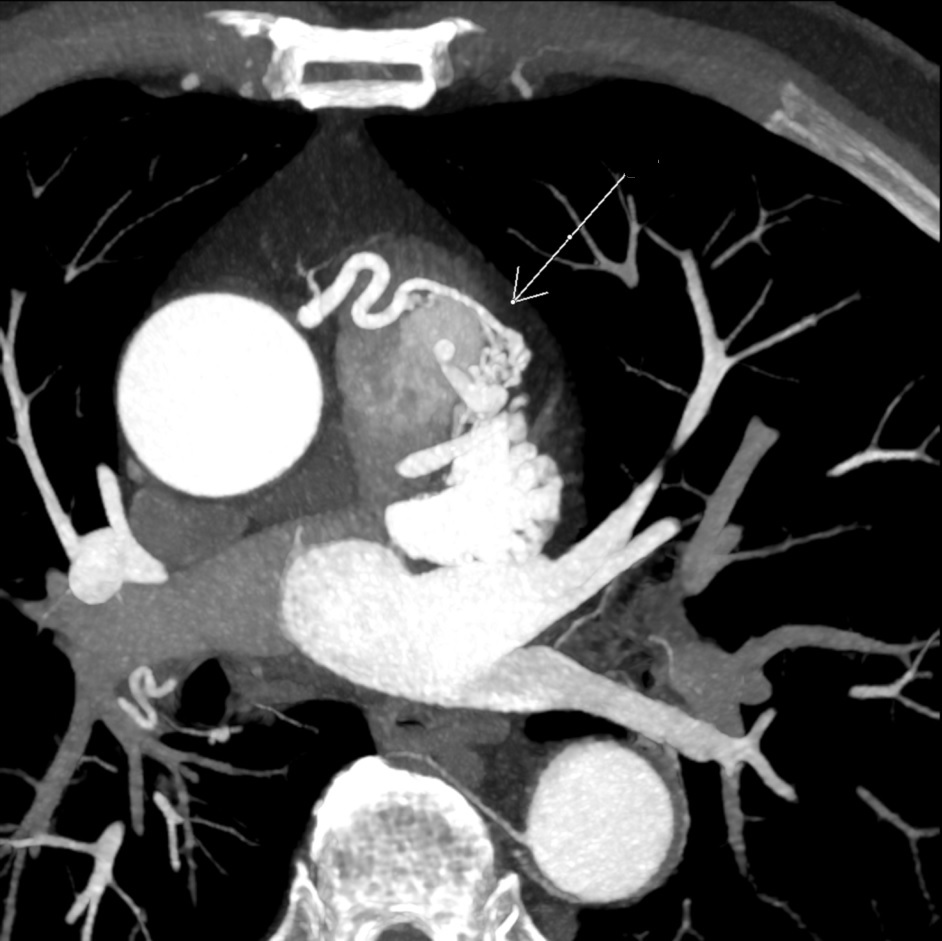

25F hx of Kawasaki and AMI at 8months old.

Right Coronary Artery (RCA): 2 fusiform aneurysms without thrombosis- 1) proximal segment 15 mm long and 8 mm in diameter with mural calcification and 2) mid segment 7 mm long and 6.5 mm in diameter at the origin of a small AM branch.